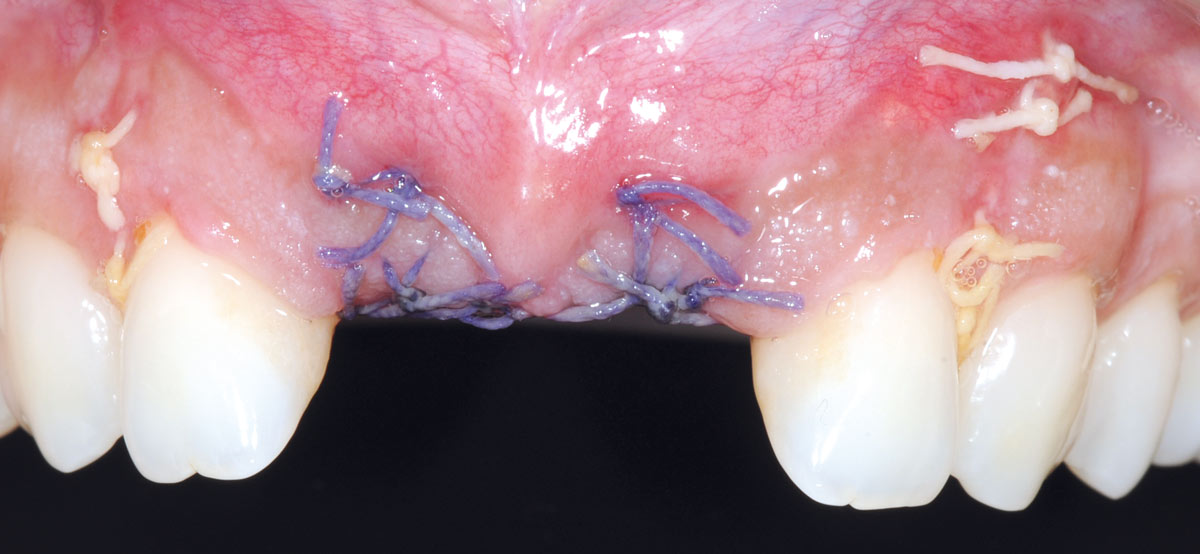

19/26 - 3 weeks post-op: eventless healingBone augmentation in aesthetic zone with maxgraft® bonering - Dr. A. Patel

20/26 - 6 weeks post-op: sutures were removedBone augmentation in aesthetic zone with maxgraft® bonering - Dr. A. Patel